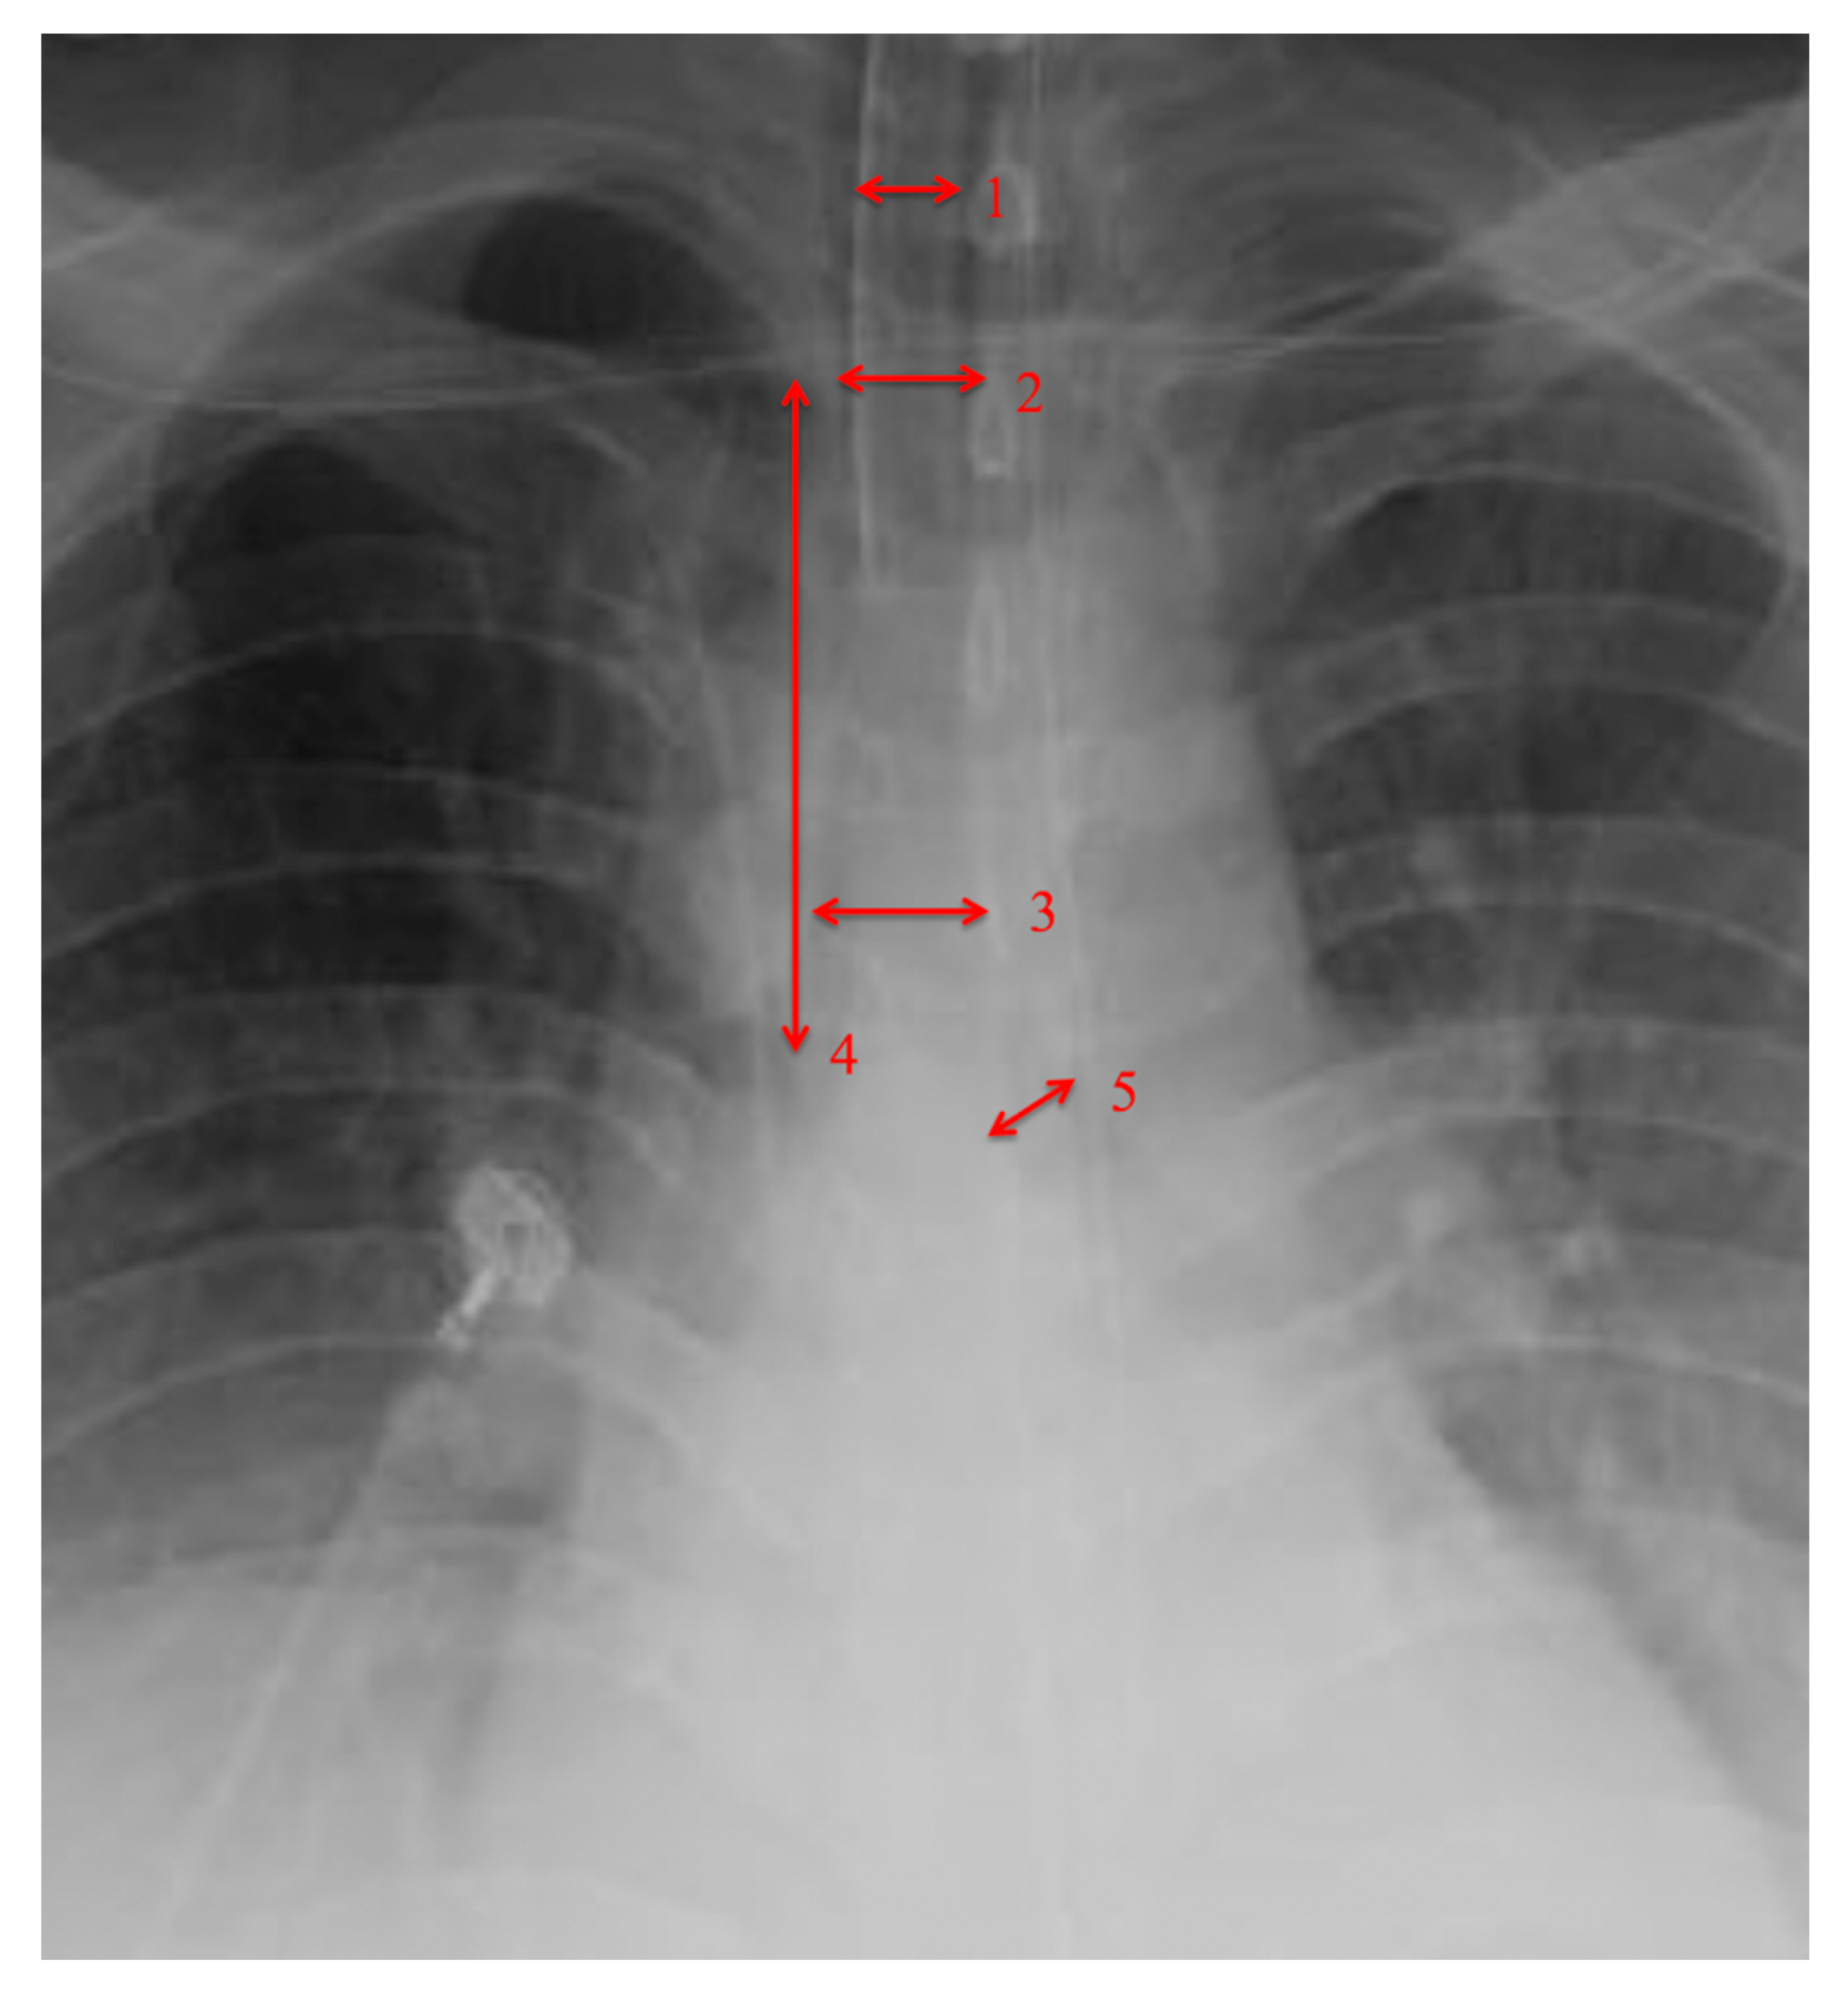

| Airway Measurement (mm) | Total n = 23 Mean (mm) (±SD) |

|---|---|

| Tracheal Diameter | 15.75 (±4.03) |

| Intrathoracic Tracheal Length | 82.09 (±20.82) |

| Left main bronchus | 12.765 (±2.85) |

| • Tracheal Diameter Measured at 1st Rib > 15 mm |

| • Tracheal diameter measured at carina > 15 mm |

| • Intrathoracic Tracheal length from 1st rib to carina > 80 mm |

| • Left main-stem bronchus diameter > 10 mm |